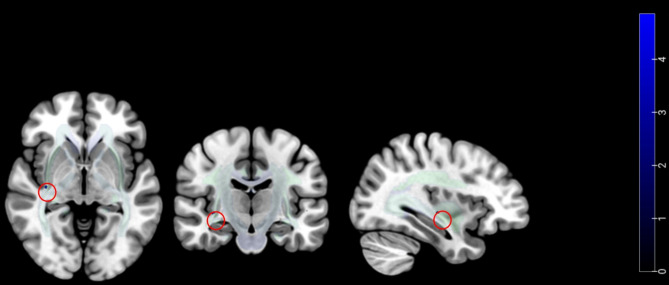

Fig. 1.

Compared to the CM − MOH group, the CM + MOH group exhibited a significant reduction in gray matter volume in the left parahippocampal gyrus (A) and the right middle occipital gyrus (B). It also had significantly lower ALFF values in the left dorsolateral superior frontal gyrus (C) and the left supplementary motor area (D)

sMRI

Compared with the CM − MOH group, the CM + MOH group exhibited a significant reduction in gray matter volume in the left parahippocampal gyrus and the right middle occipital gyrus (P < 0.001) (Table 2; Fig. 1). No regions demonstrated a significant increase in gray matter volume. In a generalized linear model adjusted for age, anxiety, depression, and sleep quality scores, these factors were not significantly associated with headache-related indicators or the frequency of medication use.